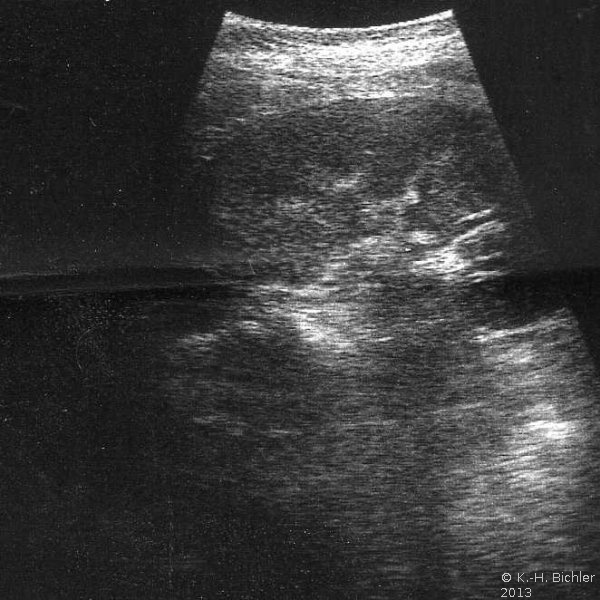

Bei einer 16-jährigen Jugendlichen wurde wegen Flankenschmerzen und sonographischem Verdacht auf einen linksseitigen zystischen Nierentumor die Freilegung durchgeführt (Abbildung 3). Dabei fand sich ein zystischer Tumor (Abbildung 4). Die histologische Untersuchung ergab eine multizystische, dysplastische Nierendegeneration.

Da die unilaterale multizystische Nierendysplasie nicht immer vergrößert ist, fallen derartige Tumoren unter Umständen erst im Erwachsenenalter anlässlich Untersuchungen aufgrund anderer Erkrankungen auf. Die Organe werden zumeist wegen der Differentialdiagnose zum zystischen Nierenzellkarzinom entfernt.